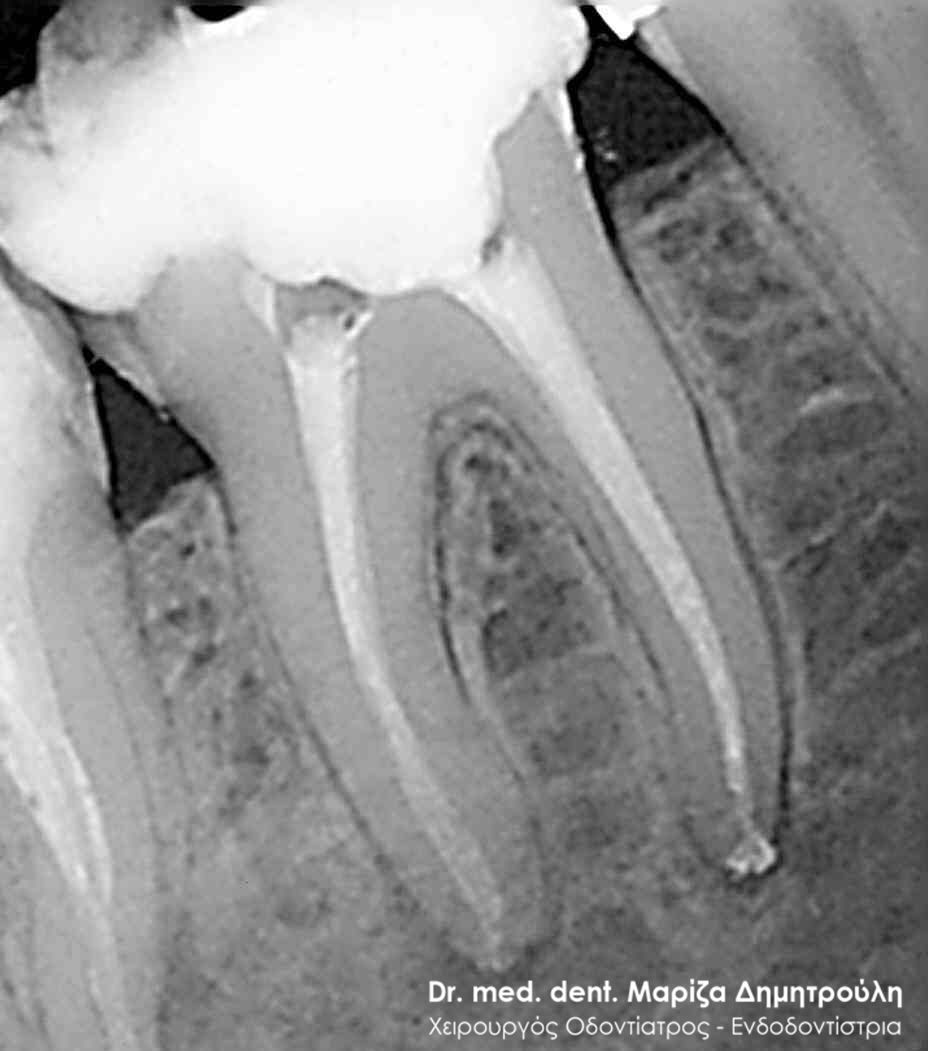

Περιστατικά – Απονεύρωση δοντιού

Παρακάτω παρατίθονται μερικά περιστατικά μετά την ολοκλήρωση της απονεύρωσης δοντιού.

Κάτω γομφίος με κεκαμμένες ρίζες

Άνω γομφίος με έντονα κεκαμμένες ρίζες

Μονόριζο δόντι με 3 ριζικούς σωλήνες

Κάτω γομφίος